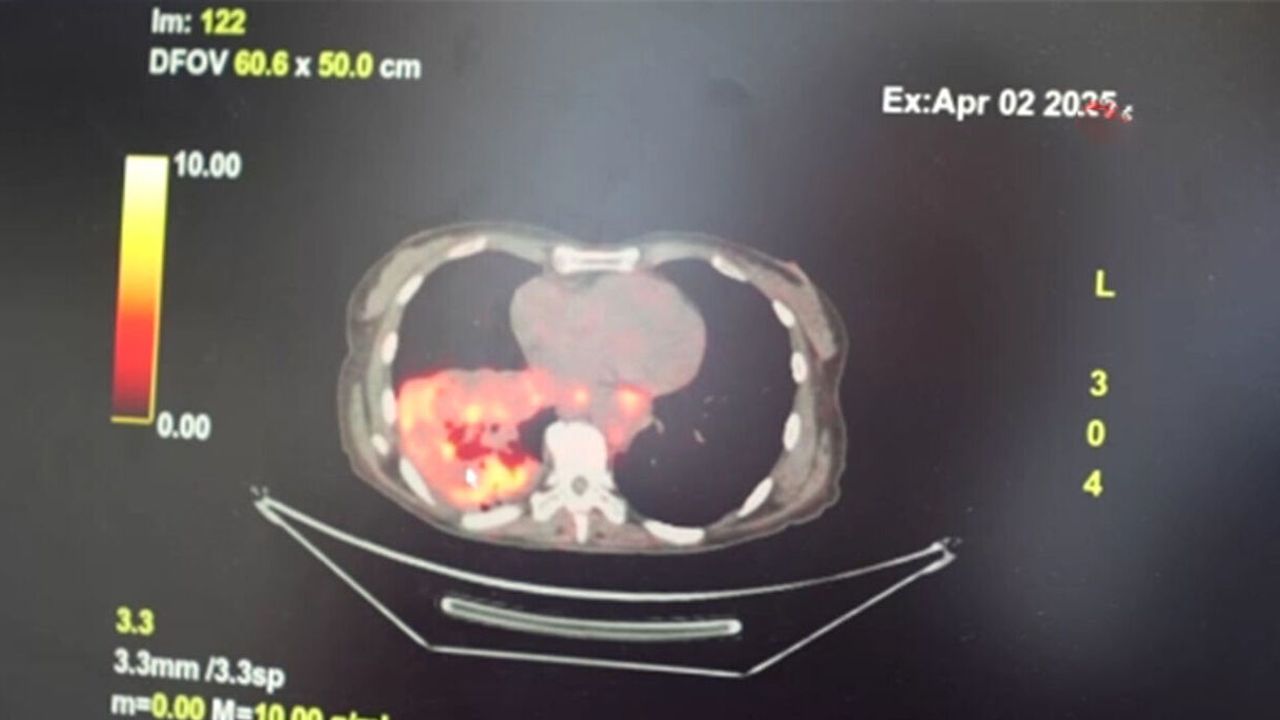

Dünyanın en prestijli tıp dergilerinden yayımlanan bir araştırma üzerinde açıklama yapan Prof. Dr. Şevket Özkaya, araştırmaya göre, sigara içmeyenlerde en sık görülen tür olan akciğer adenokarsinomu, kadınlarda akciğer kanserlerinin yaklaşık yüzde 60’ını oluşturduğunu söyledi. Prof. Dr. Özkaya, sigara dışındaki risk faktörlerinin başında radon gazının geldiğine dikkat çekerek, "Radon gazı, evlerimizde farkında olmadan soluduğumuz, renksiz, kokusuz, tatsız ve radyoaktif bir gazdır. Müsaade edilen değerlerin üzerinde solunduğunda akciğer kanseri riskini artırıyor. Radon gazı özellikle taş, toprak ve çimento gibi yapı malzemelerinde doğal olarak bulunuyor. Bu maddelerden ortama sürekli yayılan gaz, solunum yoluyla akciğerlere ulaşıyor" ifadelerini kullandı. Evlerin yapıldığı arazilerde bulunan doğal uranyumun radona dönüşmesiyle bu gazın evlerin zemin katlarından iç ortama sızabildiğini vurgulayan Özkaya, bu durumun bölgeden bölgeye ve ülkeden ülkeye farklılık gösterdiğini kaydetti. Özellikle soğuk ve rüzgarlı havalarda, evin iç basıncının düşük, dış basıncın yüksek olması nedeniyle radon gazının iç ortamdaki oranının arttığını ifade etti.